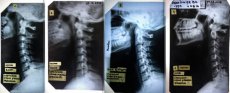

Лучанка Валентина Горайчук потребує допомоги. Дівчина збирає кошти, аби поїхати на діагностику до Києва. Бо у Луцьку, за її словами, лікарі допомогти їй не можуть.

Без корсета шия не тримається! А в ньому стає нестерпно.

В мене є попередній діагноз професора вертебролога зі Львову, пов'язаний з динамічною патологією. М'язи шиї не слухаються. Хвороба не христоматійна, випадок мабуть одиничний. Я в розпачі. Пишіть, якщо хтось щось про таке чув або знає! Луцькі лікарі розводять руками, або не допомагають і діагноз не підтверджують. Всі, хто мене знає, дуже багато людей - можуть підтвердити, що я НЕ видумую і проблеми були ще в школі, в інституті рік не могла ходити, я лежала в лікарнях неодноразово», - пише дівчина.